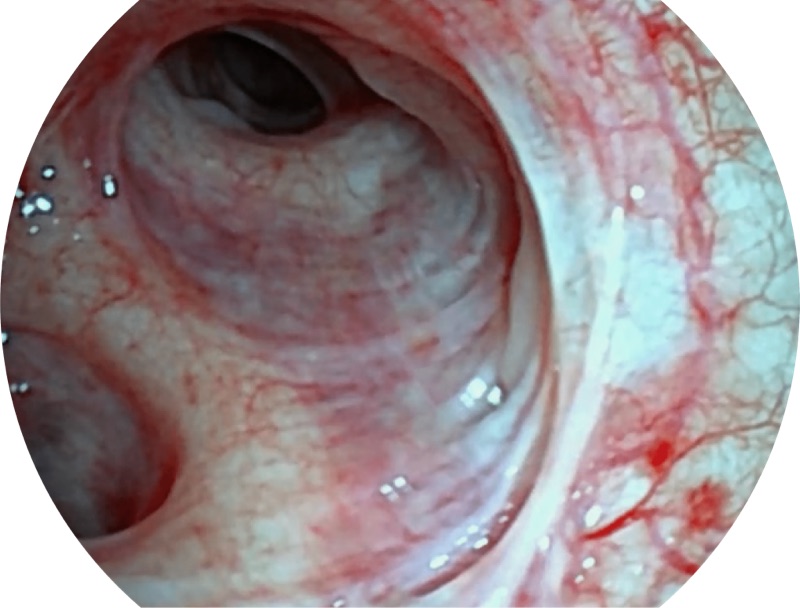

VIST